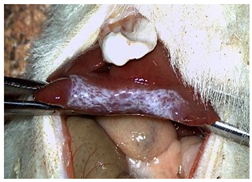

The CA + PLA patch proved effective in achieving rapid hemostasis. Upon contact with the bleeding liver, it quickly polymerized and adhered, forming a hardened, shell-like barrier that immediately stopped blood flow. Observations at PO day 50 showed that the patch remained intact on the resection plane, alongside mild to moderate abdominal adhesions. By PO day 100, while the omentum largely covered the resection site, approximately 40% of the patch had degraded. By PO day 150, peritoneal adhesions were more significant (including stomach and small bowel involvement in two instances), yet the patch itself had undergone substantial degradation, with over 80% of its original size resorbed.

For the C group, the liver resection site showed minimal scarring and adhesions, consisting mainly of omental strips attached to the resected surface.

The subjects in the T group macroscopically displayed the fibrinogen/thrombin patch present at the resection plane at all time intervals. The patch appeared to thin over time, indicating its bioresorbable nature. Notably, this group developed the fewest peritoneal adhesions.

Table 2 illustrates the appearance of the hepatic resection plane for each study group at hemostasis and on postoperative days 50, 100, and 150.